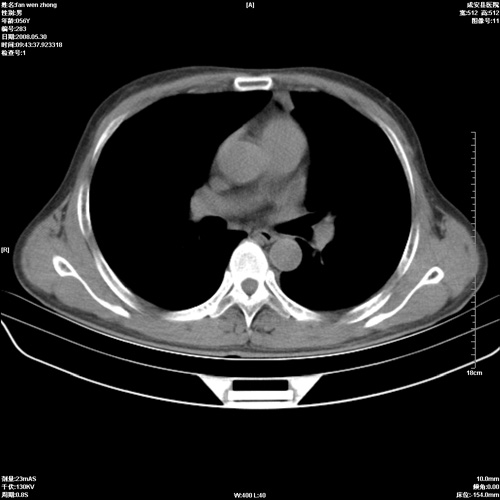

病人 男 56岁 一周前高热,体温达39-40度,经抗炎治疗后,体温渐降,达37,5-38度,轻微咳嗽,胸部不适 查白细胞为1.3万 行ct检查,请分析。

双肺内可见多发结节状病灶,并见小空洞,病人高热,白血球增高,应该是典型的迁徙性肺脓肿(多为金黄色葡萄球菌感染)。查一下口腔等其它部位有无感染灶。

双肺内可见多发结节状病灶,并见小空洞,病人高热,白血球增高,应该是典型的迁徙性肺脓肿(多为金黄色葡萄球菌感染)。建议治疗后复查.